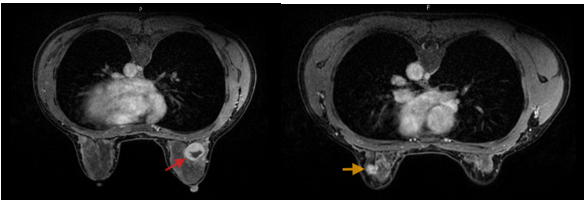

Hình 2. Hình ảnh MRI: Vú phải: Vị trí khoảng 11h, cách núm vú 35mm, có tổn thương dạng nang phức hợp kích thước 26x25x27mm, bờ đều ranh giới rõ, thành dày không đều và ngấm thuốc sau tiêm - BIRADs 4A (mũi tên đỏ). Vú trái: Vị trí khoảng 1h, cách núm vú 45mm có nốt tổn thương kích thước 18x13x9mm, bờ tua gai, co kéo nhẹ nhu mô tuyến vú lân cận; không thấy xâm lấn da và thành ngực - BIRADs 4C (mũi tên vàng).